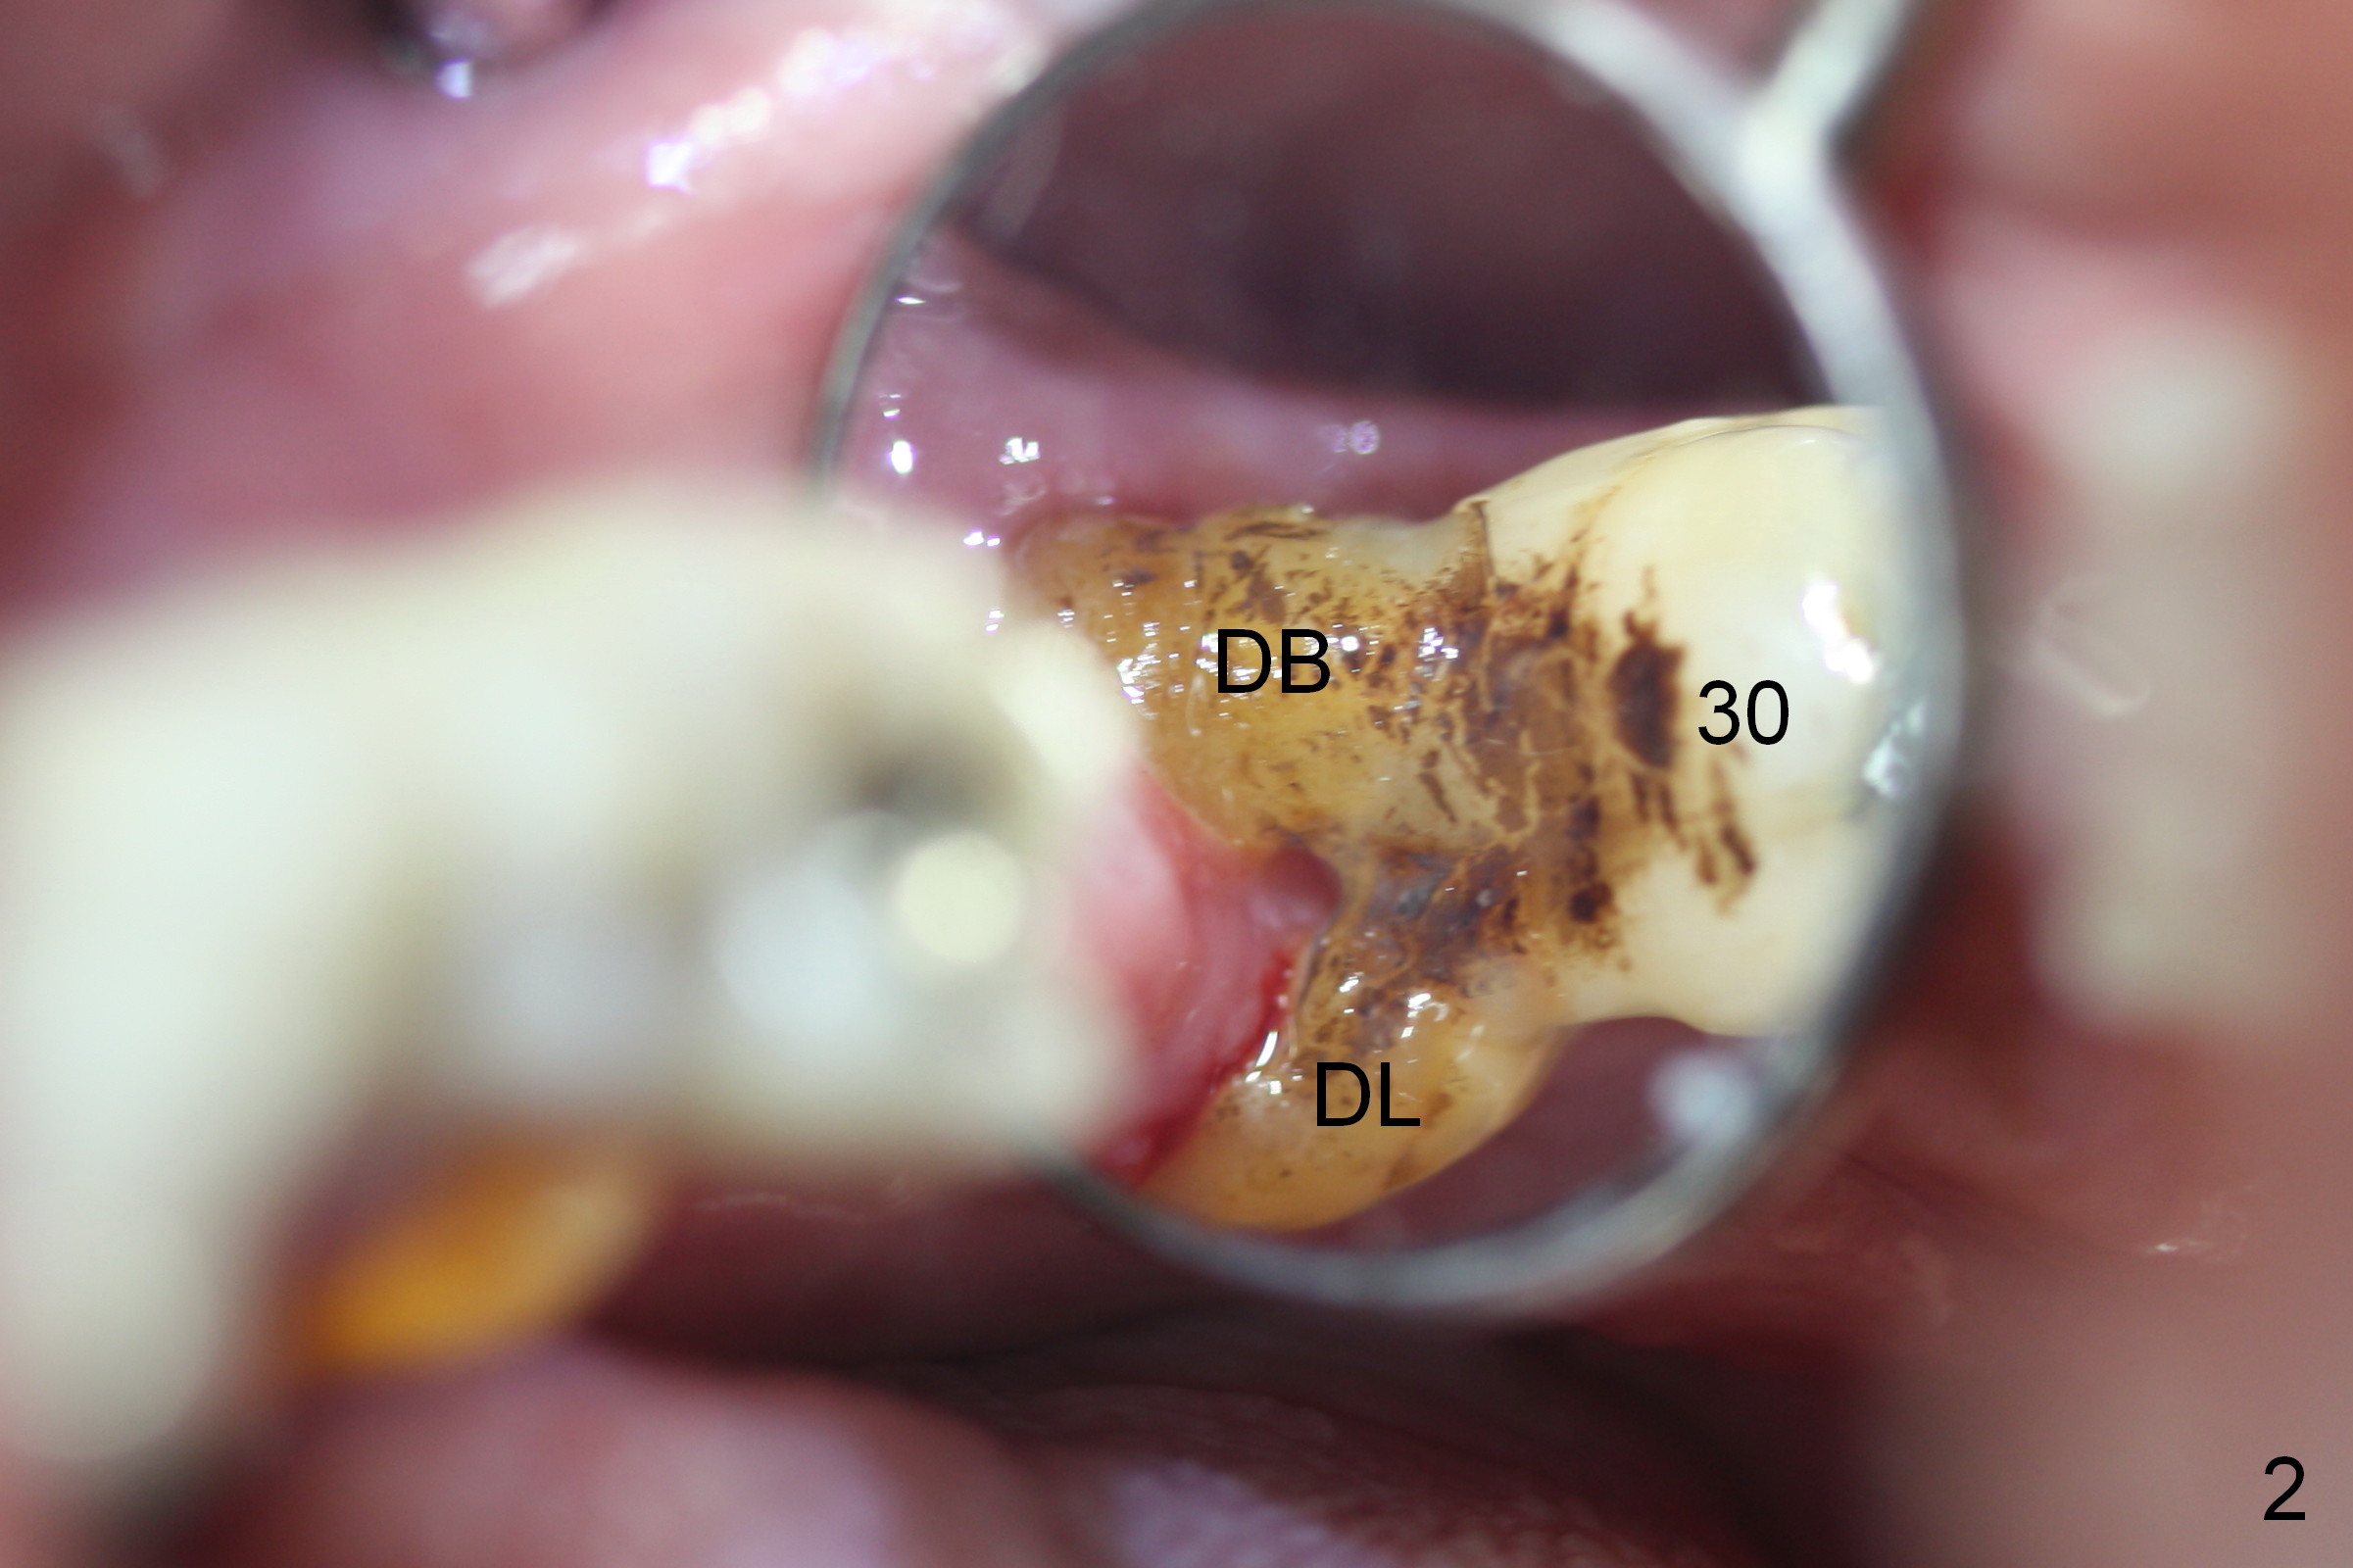

Severe Gingival Recession

A 74-year-old man requests the 5th implant placement at #30. He feels that immediate implant (1,2) is associated with less pain than delayed one. He is looking forward the immediate implant at #30. This tooth has severe gingival recession (Fig.1,2): the mesial (M), distobuccal (DB) and distolingual (DL) roots having been exposed. The socket with the tripod septum will be treated with Metronidazole, randomly selected by case sequence. One of challenges to implant placement is to handle keratinized (K) and non-keratinized (N) gingival tissues. After tooth removal and infection resolution, it is expected that some of non-keratinized tissue can be converted to the keratinized one to promote health of the implant. Fabricate a tightly fit immediate provisional to cover the irregularly-shaped socket. Use a nonresorbable membrane where the provisional is unable to cover the socket. Preop PA is to be taken for design. Bone height should be limited.